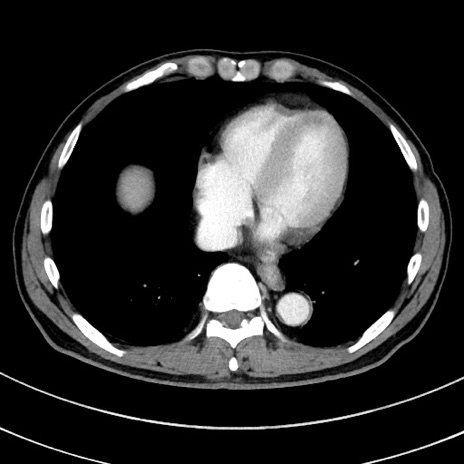

症例8(横断像)

【症例】 60歳代男性

【主訴】 黒色吐物

【現病歴】 4日前から嘔気自覚、2日前の朝食後にも嘔気あり、自分で手で嘔吐反射起こし嘔吐したところ血が混ざっていたため受診。

【既往歴】 5年前汎発性腹膜炎を伴う急性虫垂炎で手術、高血圧、前立腺肥大症、高脂血症

【身体所見】 腹部正中に手術癩痕あり 腹部平坦・軟圧痛なし膨満感あり

【データ】WBC 8400、CRP 4.54